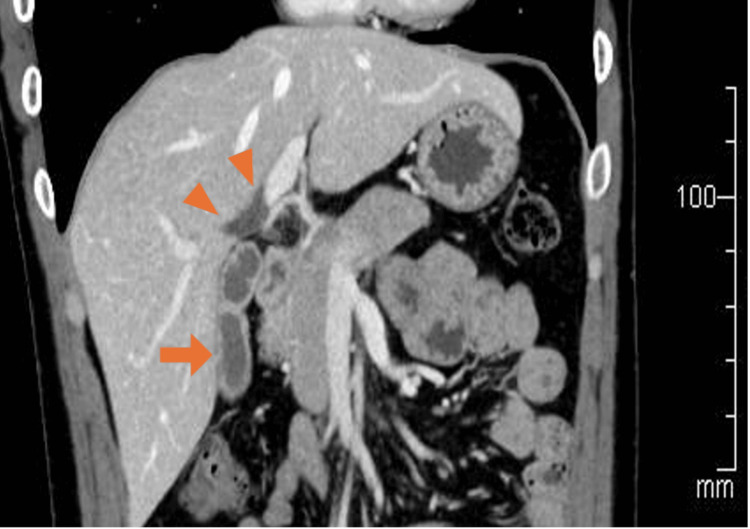

A 30-year-old man presented to our department with intermittent right upper abdominal pain occurring every few months for 10 years. He had a history of taking sodium valproate for epilepsy. He smoked approximately 20 cigarettes per day and had no history of alcohol consumption. Laboratory tests revealed neither inflammatory reactions nor elevated hepatobiliary enzyme levels. Contrast-enhanced computed tomography (CECT) showed a thickening of the gallbladder wall, suggesting chronic cholecystitis. Additionally, the right and left hepatic ducts in the hilar area were dilated, with a maximum diameter of 8 mm; however, the dilation of the extrahepatic bile duct was not significant (Figure 1). Similar to the CECT findings, magnetic resonance cholangiopancreatography (MRCP) showed dilation of the hilar bile duct. Furthermore, MRCP revealed flexed fusion between the ventral and dorsal pancreatic ducts (Figure 2a). Endoscopic retrograde cholangiopancreatography (ERCP) revealed the same findings, with mildly dilated hepatic ducts in the hilar area and an abnormally curved main pancreatic duct in the pancreatic head region (Figures 2b, 2c). During the ERCP, the collected bile showed an amylase level of 6,311 international units (IU)/L, exceeding the normal value of less than 1,000 IU/L [ref. 7]. Meanwhile, the lipase level measured 16,000 IU/L, for which the normal range remains undefined.

According to the diagnostic criteria for CBD, this entity is specifically defined as biliary dilatation in conjunction with PBM. In other words, it refers to “bile duct dilatation with pancreaticobiliary confluence abnormality,” which includes Todani type I-a, type I-c, and type IV-a. The definition of biliary dilatation does not specify the diameter of the intrahepatic bile ducts but that of the common bile duct (≥6.4 mm) [ref. 8]. In this case, mild dilation of the hilar hepatic ducts was detected using various modalities, such as CECT, MRCP, and ERCP. The hilar hepatic bile ducts were locally dilated (8 mm); however, they were difficult to categorize according to the Todani classification. Therefore, this type of intrahepatic biliary dilation would be considered an unclassified and rare form of CBD.